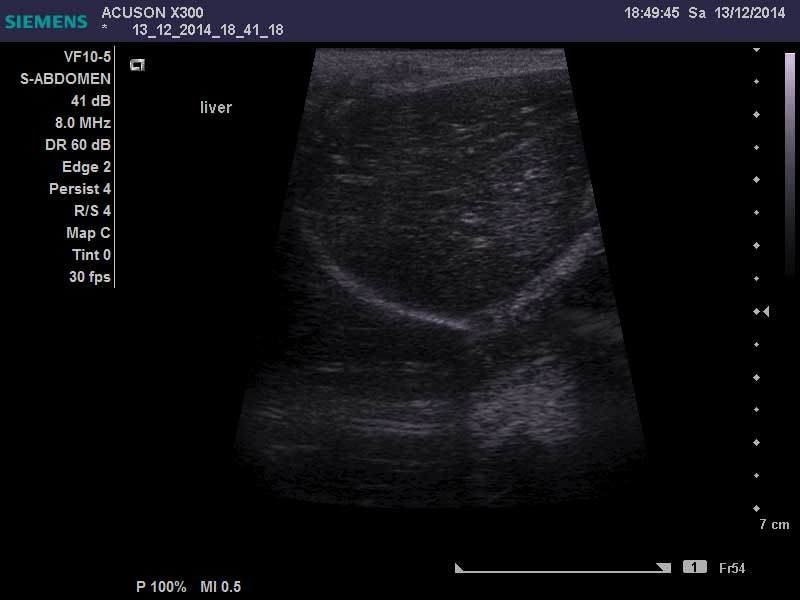

回生在醫院一共住了16天調養身體,X光及超音波顯示她的2顆腎都長了腫瘤也變形,醫生也無法進行手術、貧血的狀況也一直沒有良好的改善...醫生建議秀雲姐帶回去做安寧照護,回生已於12/27回到喵喵茶,秀雲姐這幾天也有持續帶回生回診治療,希望回生可以好好渡過每一天!!!